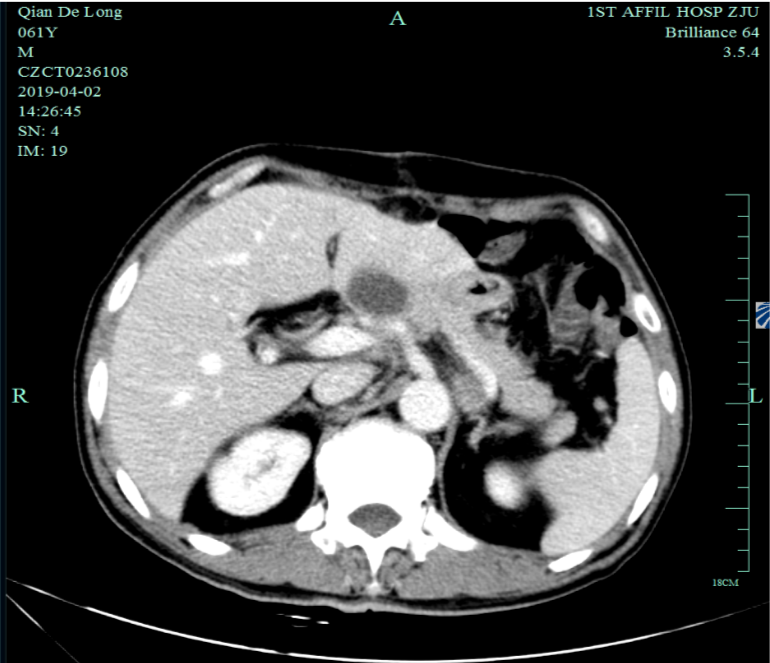

入我院后全面进行评估(2019.4):全腹部CT平扫+增强评估提示腹膜后,胰腺周围多发淋巴结增大,淋巴结转移考虑。

2019-4-2至2019-6-5行SOX+赫赛汀 q3w 4周期联合化疗:具体为奥沙利铂220mgD1、替吉奥3# BID D1-14、赫赛汀400mg(首次)+300mg。

一线化疗疗效评估(2019.6 vs 2019.4):胃癌术后改变。影像评估CR。